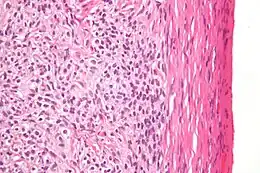

Fort grossissement d'un thécome, coloration à l'hématoxyline et à l'éosine.

Au microscope, les cellules tumorales ont un cytoplasme abondant rempli de lipides.